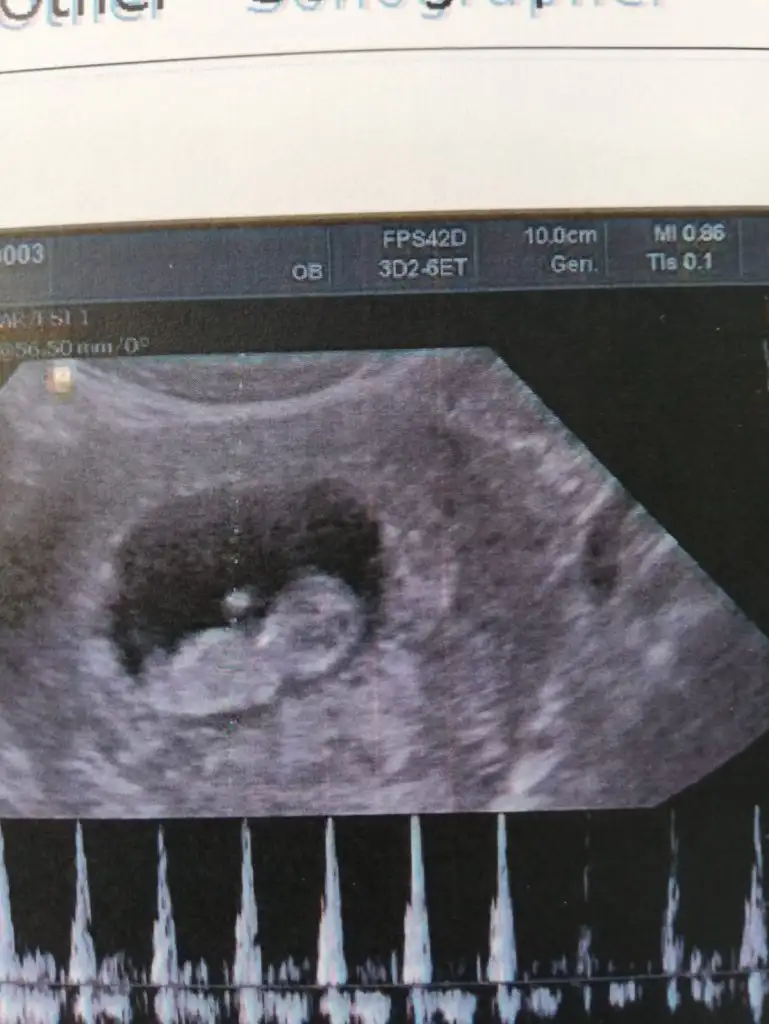

dr soylemeden siz gorun genital nub teorisi ( bebegin cinsiyeti)

Kuzenimin bebişi 10 haftalık.. Cinsiyet tahmini yapar mısınız kızlar... Benimkini doğru bilmiştiniz

Buna göre erkek ama tutmaya biliyor benim kızlarda bu yöndeydi solda idi ikiz kızlarım oldu